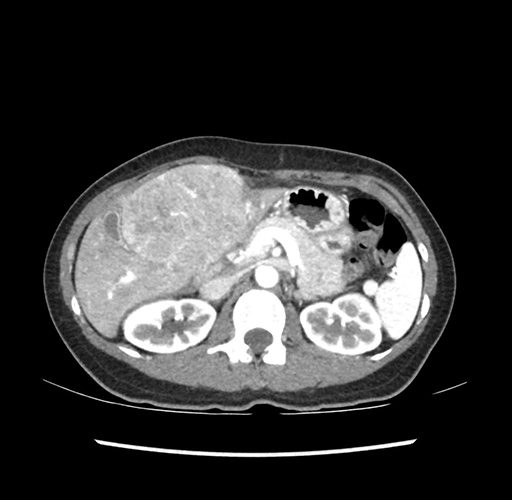

Imaging Analysis

Look through the patient's CT scan to identify any areas of concern for the necessary procedure.

Based on your CT findings, which issue(s) would give reason for "planned slowing down moment(s)" in this case?

Considering a standard left lateral sectionectomy procedure, what step(s) of the operation would you do differently in this case ?